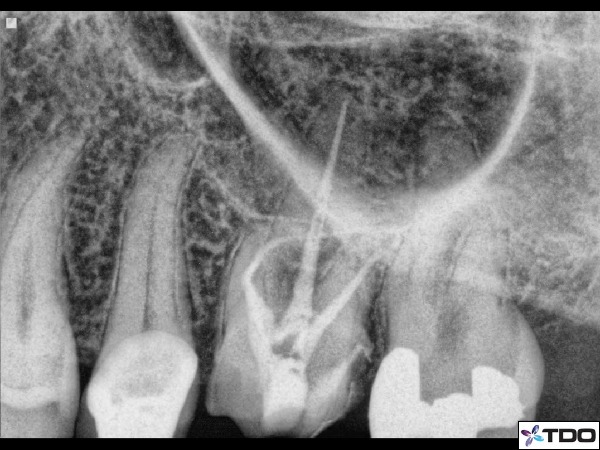

Another example would be in retreatment scenarios that have a post to remove. We would need to open larger coronally in order to gain access to the lateral sides of the post/cements/dentin to dislodge it (figure 5).

Figure 5: Here is a case in which the MB and DB canals had a silver point and the P canal had a wide post. I therefore needed to open the access larger in order to use the various instruments to retrieve the silver points and the post. Even though you cannot see the access size with the crown in place, this is a good example of a retreatment case that will require a larger coronal access. The radiograph in the upper right is with all materials removed and calcium hydroxide in place. The lower left if the immediate post-op x-ray.